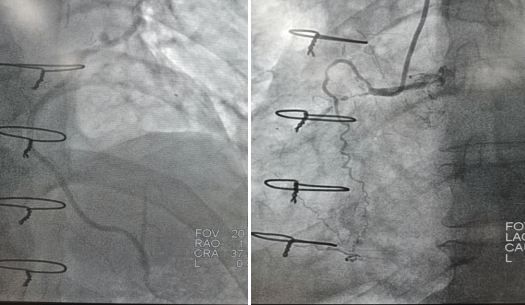

2022年9月16日行冠脈造影術(shù),造影結(jié)果示:左主干末端99%狹窄,LAD近段100%閉塞,LCX開口及近段95%狹窄,乳內(nèi)動(dòng)脈-左前降支血管通暢,RCA近段100%閉塞,大隱靜脈橋血管未見,考慮閉塞。

心血管病院吳棟梁院長(zhǎng)、CCU李新國(guó)副主任、心血管內(nèi)科二病區(qū)趙娟副主任、王端樂主治醫(yī)師、宋睿主治醫(yī)師介入團(tuán)隊(duì)造影后認(rèn)真研究患者的病情和影像資料,決定開通閉塞長(zhǎng)達(dá)11年的右冠狀動(dòng)脈,精確選擇器械,選擇同軸性及支撐力均好的指引導(dǎo)管,術(shù)中選用微導(dǎo)管輔助,軟、硬導(dǎo)絲結(jié)合等技術(shù),聚精會(huì)神、揮汗如雨,終于歷經(jīng)3小時(shí)的努力,成功前向開通右冠狀動(dòng)脈,精準(zhǔn)選擇由遠(yuǎn)及近“鋪設(shè)”通過性較好、長(zhǎng)度合適的支架 。

(術(shù)前術(shù)后對(duì)比)